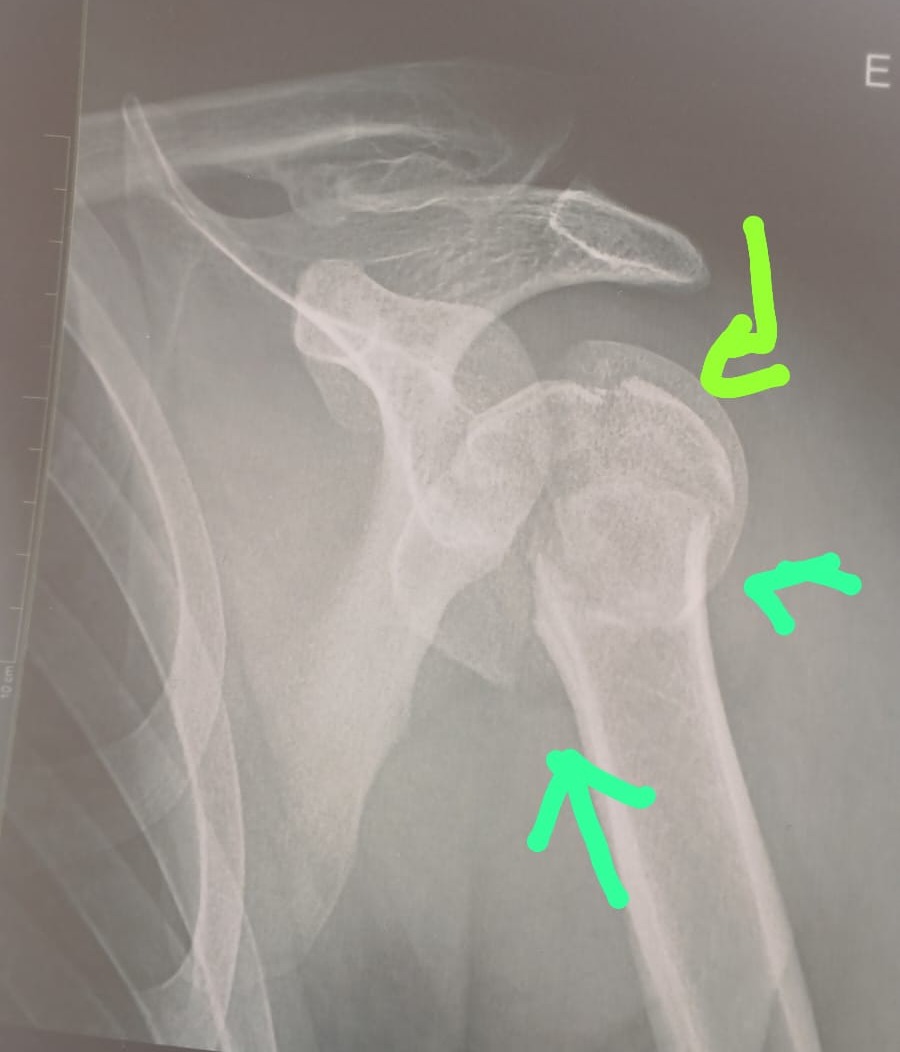

Foto: Raio-X da fratura do ombro de Clerio - Acervo da família

O jovem de 28 anos precisa realizar com urgência uma “osteossíntese de fratura de úmero proximal”, de acordo com os documentos médicos disponibilizados por Pedro para a reportagem. A cirurgia serve para realinhar e fixar fragmentos ósseos no ombro. Por causa da demora, eles entraram com um processo na Justiça.